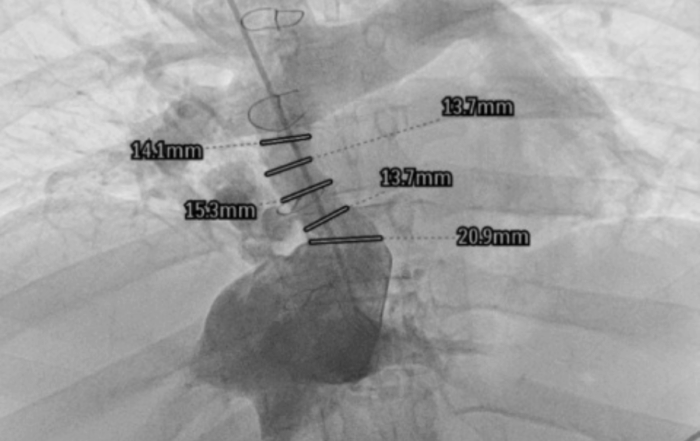

Kardiologia interwencyjna. Pierwszy taki zabieg na Mazowszu i jeden z nielicznych w Polsce

Dzięki multidyscyplinarnemu zapleczu i współpracy specjalistów z różnych dziedzin w UCKWUM po raz pierwszy przeprowadzono zabieg przeznaczyniowego poszerzenia tunelu fontanowskiego [...]